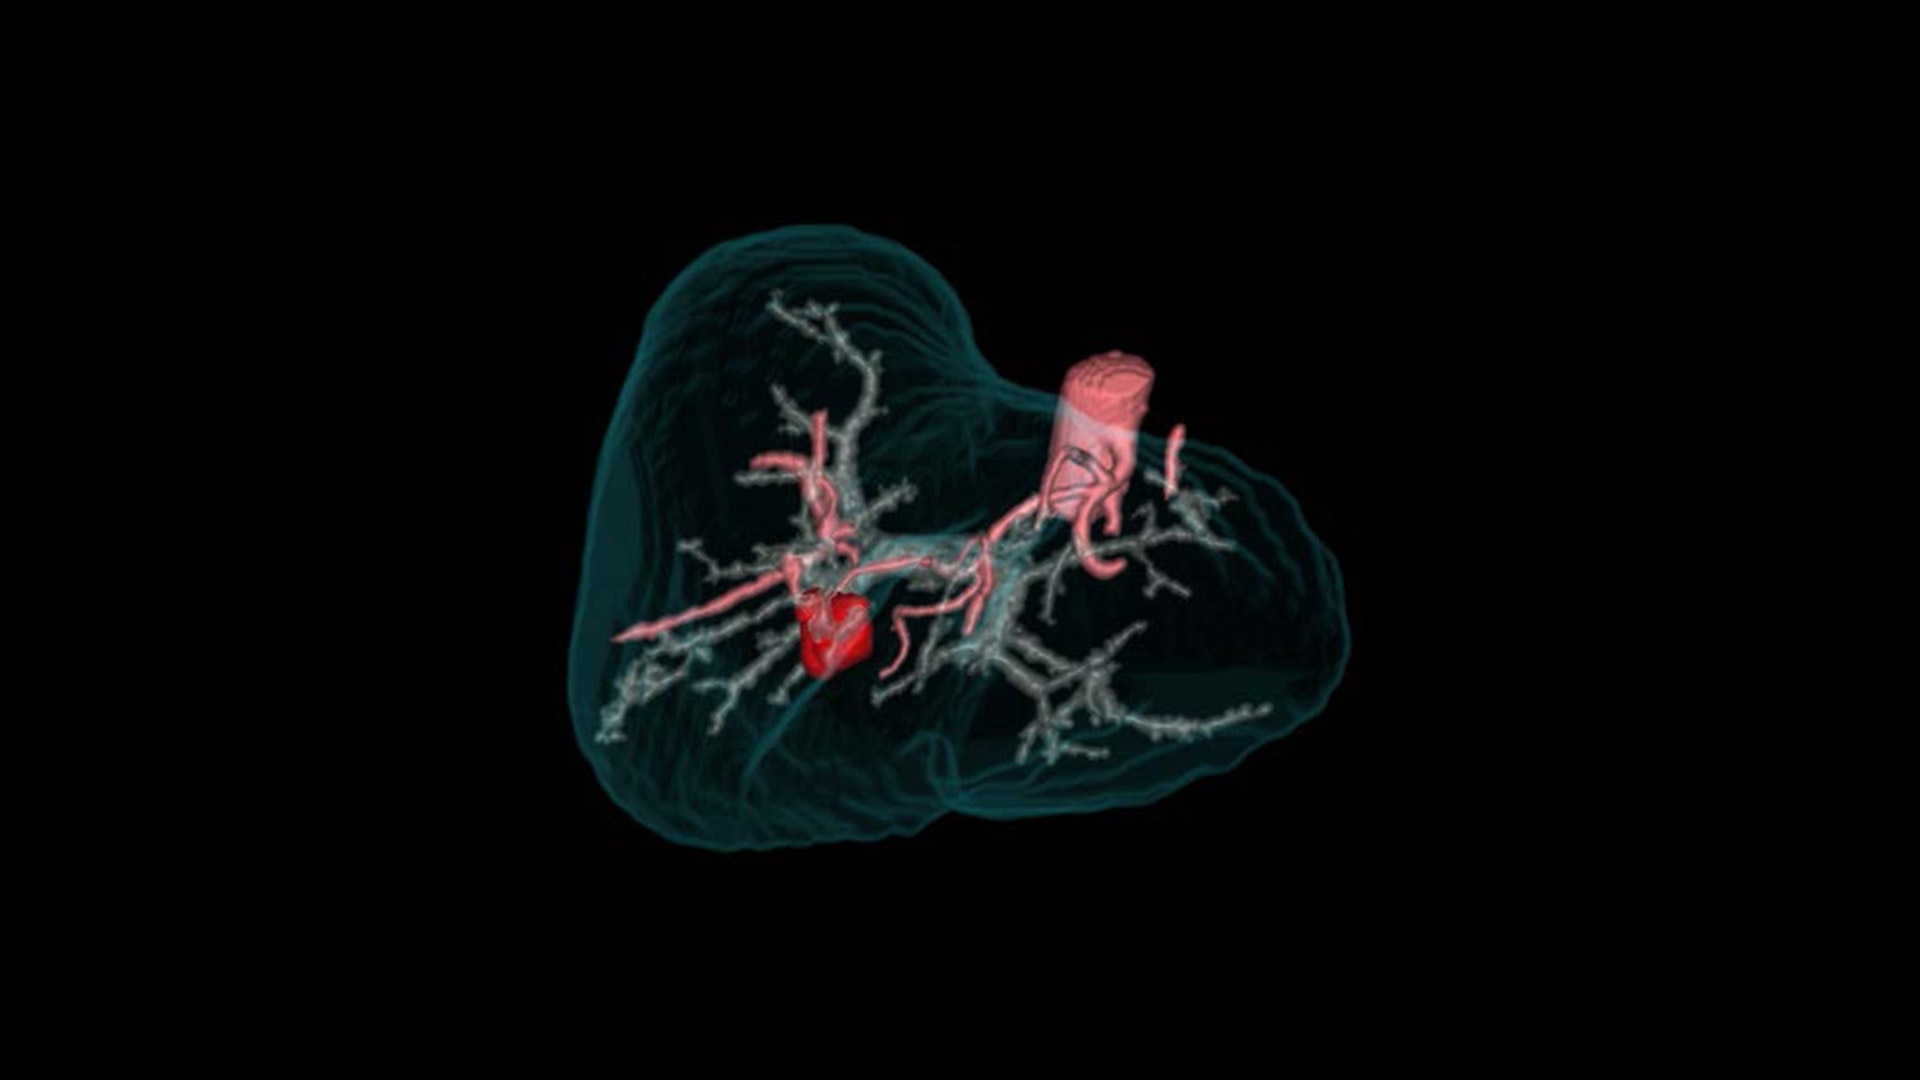

Advanced Visualization

Elevate your CT imaging with our collection of advanced visualization applications that assist reading, automate post-processing and streamline imaging review.